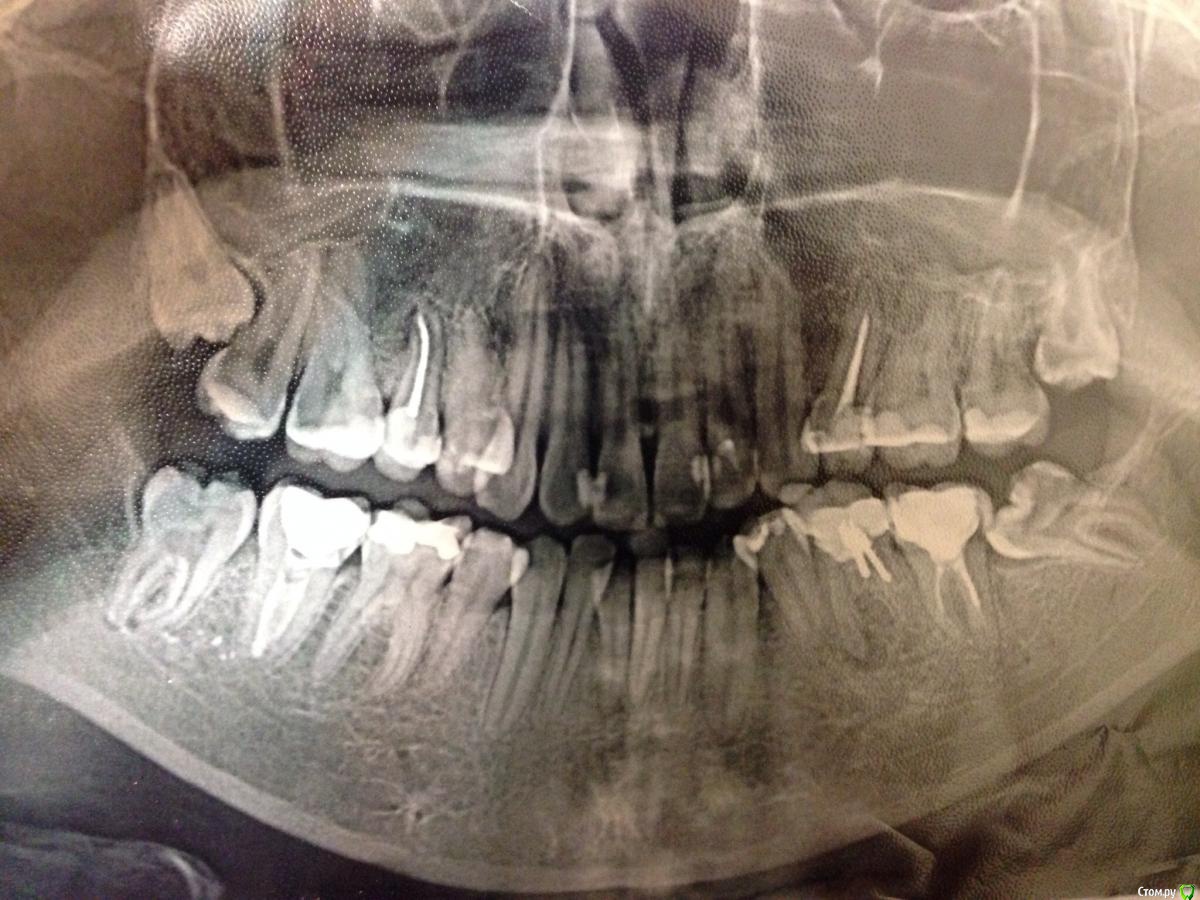

Здравствуйте! Вопрос по поводу удаления 6 снизу слева. Так как там воспаление, в случае невозможности лечения зуб придется удалить. Но я планирую ортодонтическое лечение. Как я понимаю имплантация возможна только после ортодонтического лечения. В моем случае срок начала лечения может быть и через несколько месяцев и через несколько лет, не говоря уже о дате завершения лечения. Так вот, если я удалю зуб сейчас а имплант буду ставить только через несколько лет, не изменится ли костная ткань настолько ,что имплант будет невозможно поставить? И есть ли способы избежать этого? Также, насчет 8 справа сверху, насколько сложным будет ее удаление?

8ка наверху - без проблемное удаление. 2-3 минуты на все.

Имплантироваться можно и во время ортодонтического лечения, если ортодонт понимает куда встанут зубы и где должен стоять имплантат.